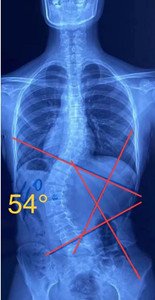

单向侧弯

如果是单向侧弯的患者,(腰弯或者胸弯),躺在床上,应向患侧处进行卧位,侧卧在你弯弧的凹侧,让它下坠打开。